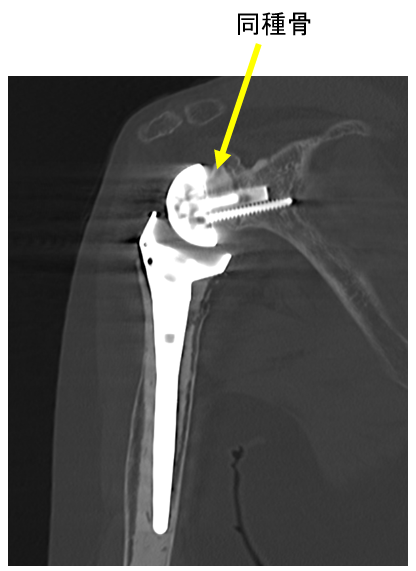

手術して6年でのCT